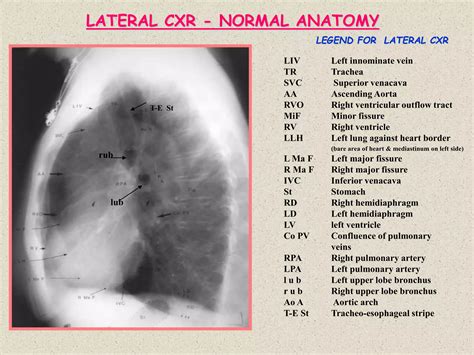

Interpreting a Normal Lateral Cxr

Interpreting a Normal Lateral Cxr requires a trained eye and a deep understanding of anatomy. Radiologists look for various indicators to assess the health of the chest cavity. Some key elements to consider include:

• Lung Fields: The lungs should appear clear, with no signs of consolidation, masses, or fluid. Any opacities or abnormalities can indicate infections, tumors, or other conditions.

• Heart Size and Shape: The heart should be of normal size and shape. An enlarged heart (cardiomegaly) can indicate conditions like heart failure or hypertension.

• Diaphragm: The diaphragm should be clearly visible and in its normal position. Elevation or flattening of the diaphragm can indicate underlying issues.

• Bones and Soft Tissues: The ribs, spine, and soft tissues should be examined for any fractures, dislocations, or masses.

• Mediastinum: The mediastinum, the central compartment of the thoracic cavity, should be assessed for any widening or abnormalities, which can indicate conditions like lymphadenopathy or aortic aneurysms.

Radiologists use a systematic approach to interpret Normal Lateral Cxr images, ensuring that all relevant structures are examined. This includes: